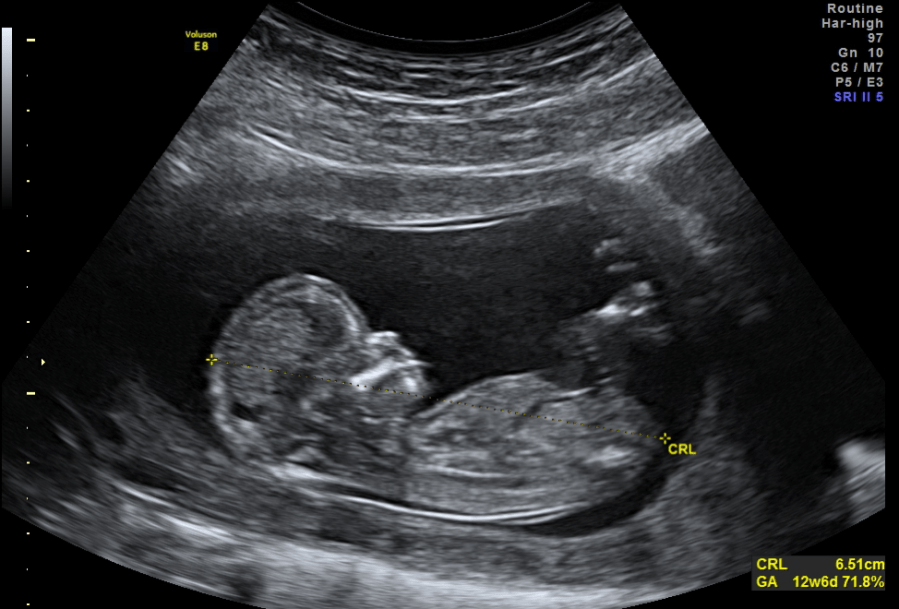

The piezoelectric effect also found similar application on a much smaller scale than war-time submarines. Medical ultrasound also uses the premise of generating sound and detecting the ultimate reflection. In this case, a piezoelectric material is electrically charged to oscillate, emitting ultrasound. Ultrasonic waves are soundwaves with such a high frequency that humans cannot perceive them. In medical applications, the ultrasound reflects off of the internal body part and back to the noninvasive device. There, a different piezoelectric element senses and converts the sound into a digital signal, giving an image. Medical ultrasound has allowed doctors to diagnose organ issues and monitor pregnancies to better screen for complications.

Piezoelectricity give parents a heads-up about how ugly their baby will be